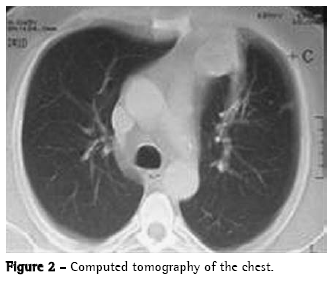

A chest X-ray revealed nodular opacities in the middle third of the left hemithorax, in lingular projection, measuring approximately five centimeters in diameter (Figure 1), confirmed through a tomography scan of the chest (Figure 2). Sputum culture for Koch's bacillus was negative, and the patient presented no reaction on the purified protein derivative test. Bronchoscopy revealed hematogenous remnants in the lingular bronchial segment, without further alterations. A transbronchial biopsy revealed a nonspecific inflammatory process. Pulmonary function test results showed mild obstructive ventilatory disorder, with a forced expiratory volume in one second of 82%.

On chest X-rays, teratoma can present as lobulated upper lung lobe tumors or intraparenchymal opacities, corresponding to the exam shown above. On tomography scans of the chest, homogeneous or heterogeneous tumors can be observed.(1-3,5,7)